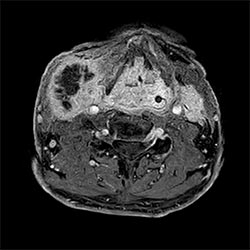

In a society where reimbursements are declining and chronic conditions lead to increased MR procedures and longer waiting times, there is ever increasing pressure on the radiology department. Today, further attempts to accelerate, compromise image quality or are limited to a narrow range of scans. Therefore, to meet the increased demand for productivity, a technology break-through in acceleration is still required. Leveraging our long standing leadership position in speed (i.e. SENSE), Philips brings compressed SENSE, a breakthrough in productivity.

Learn more about the main principles of Compressed SENSE and how it introduces a paradigm shift in productivity, how Compressed SENSE was designed around image quality, and how it advances productivity for clinical MR imaging.

Read about the experiences from Kantonsspital Winterthur (Switzerland) who experienced Compressed SENSE to be a simple yet powerful way to accelerate MRI scanning for different contrast types and sequences, in 2D as well as 3D.